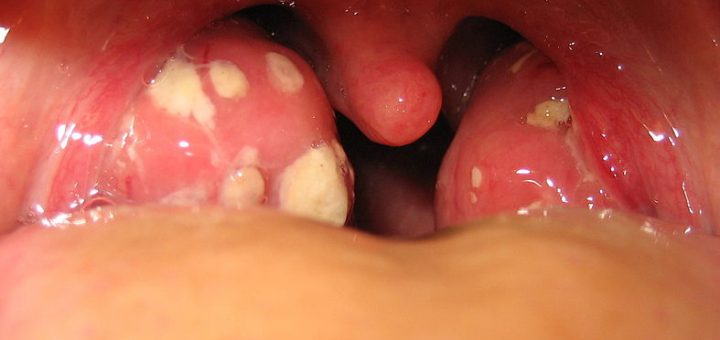

Your tonsils are two little lymph nodes that are found on either side of the back of your throat. Considering that the tonsils are there solely to keep your body from getting infected, it is rather ironic that they themselves can get infected, which is what tonsillitis is. Luckily, there are many simple home remedies for tonsillitis.